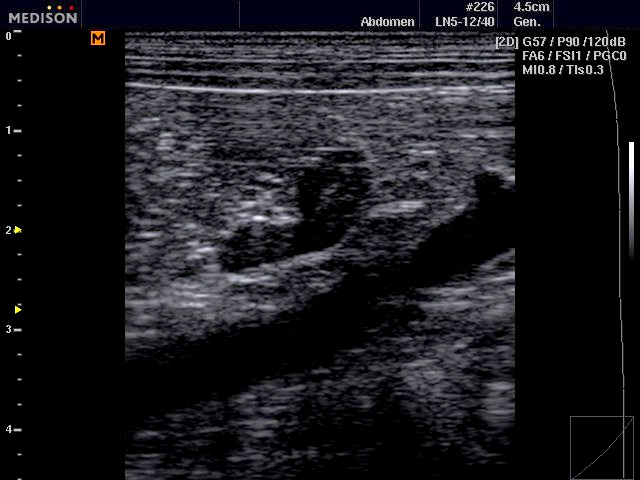

SonoVet ultrahang esetkép lineáris vizsgálófejjel